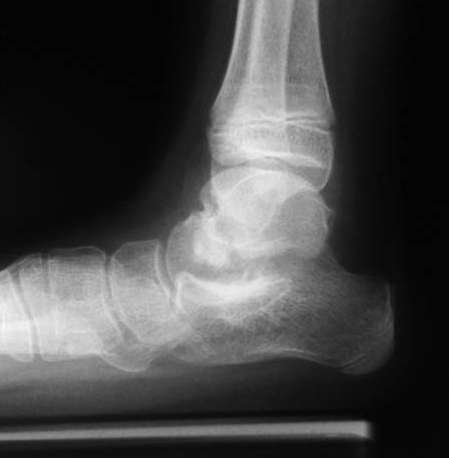

Röntgen Fuß AP und seitlich im Stand oder belastungssimuliert (Abb.1,2).

Röntgen seitlich in maximaler Plantarflexion bei Unklarheit über die Flexibilität.

Standaufnahme des oberen Sprunggelenkes: Bei Verdacht auf Instabilität oder Fehstellung des oberen Sprunggelenkes.